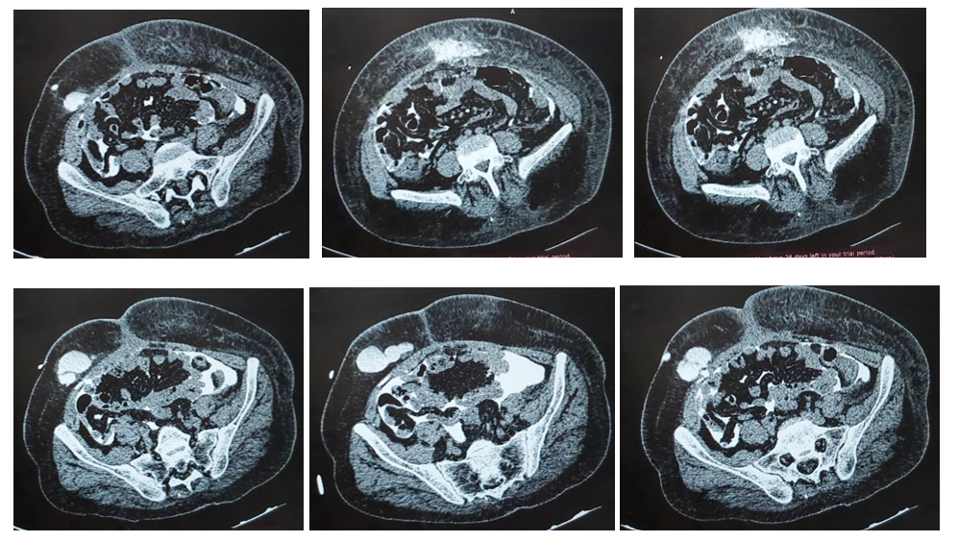

Abdominal ultrasound was unremarkable. A complementary non-injected abdominal CT scan was ordered, showing edematous infiltration of the subcutaneous cellulo-fatty tissues of the abdominal wall lateralized to the left. We supplemented this examination with CT peritoneography with injection of Gastrografine (350 mg/ml) in a volume of 100 ml, diluted in 500 ml of isotonic dialysate fluid and injected intraperitoneally 30 minutes prior to the examination, to confirm subcutaneous leakage. The CT scan showed extravasation of Gastrografine along the catheter on the right, related to a subcutaneous fistula, with diffusion into the cellulo-fatty tissues of the abdominal wall on the left, testifying to a peritoneal seal defect along the path of the new catheter (Figure 2).

Figure 2.Example caption for this image